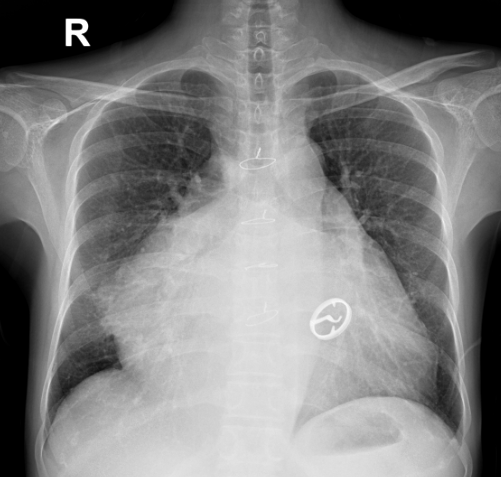

X光胸片提示巨大的心脏,大小超过正常心脏大小的2.5倍

图中圆形影像为第一次心脏手术时置换的二尖瓣人工机械瓣